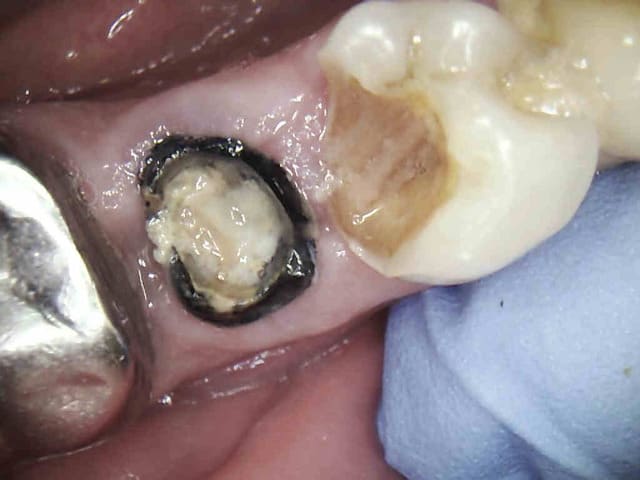

.........Et revenue aujourd'hui en urgence avec un magnifique bridge CCAM-CMU + pulpite sur 26 en option. (bridge 1 mois). Option pèche sur 14 à venir sous l'ic également.

J'y ai collé un amalgame au pouce histoire de faire plus vrai.-)))))

Costaud le full zircone

Tu vois casa je sais faire des cavités d'accès discrètes quand je veux.-))))

> Tu vois casa je sais faire des cavités d'accès discrètes quand je veux.-))))

Comment tu fais pour qu'elles soient si "nettes"? Tu passes un truc sur le plancher?

Fraise boule sur CA en remontant pour virer les surplombs, sinon j'utilise "canal pro NAOCL EXTRA" de chez coltène, pour l'irrigation ultra efficace.

Ah ben tu vois que tu peux bien bosser , sinon l'amalgame : c'est pour faire joli ?

oui, c'est très classe sur une zircone, ca fait plus vrai surtout quand le reste de la bouche en est farci.-))))